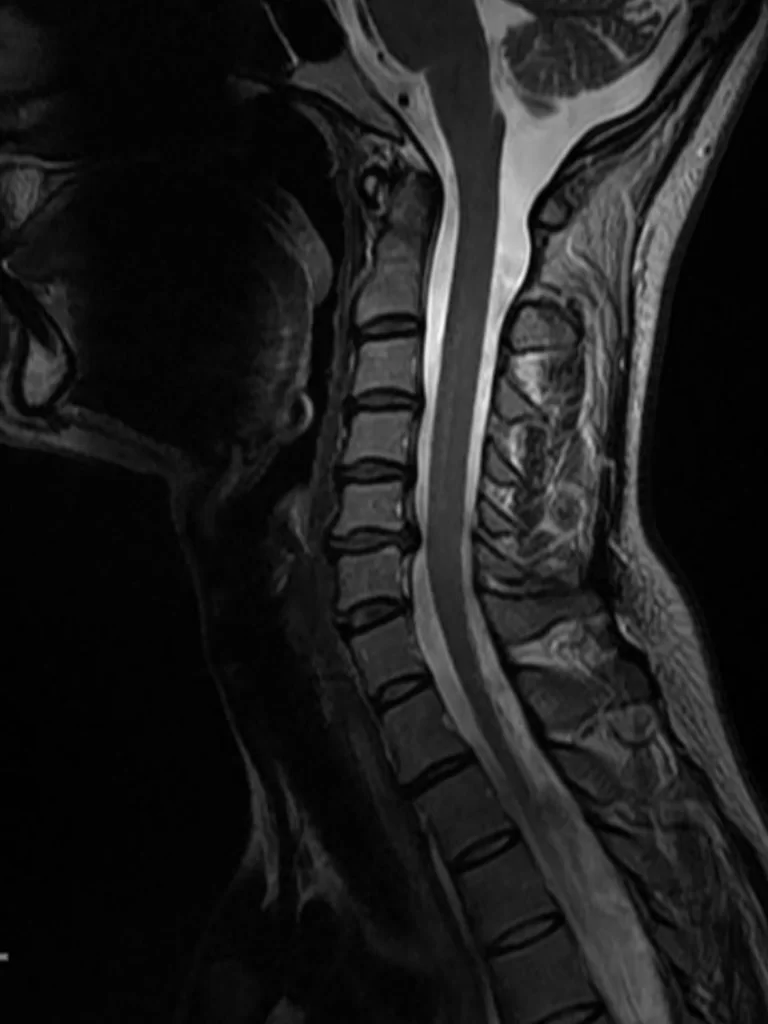

Ο απεικονιστικός έλεγχος έλεγχος με μαγνητική τομογραφία της αυχενικής μοίρας της σπονδυλικής στήλης (ΑΜΣΣ) ανέδειξε κήλη μεσοσπονδύλίου δίσκου στο επίπεδο Α5/6 και ευθειασμό της ΑΜΣΣ.

Διενεργήθη πρόσθια δισκεκτομή Α5/6 και τοποθέτηση τεχνητού δίσκου (Cadisc-C).